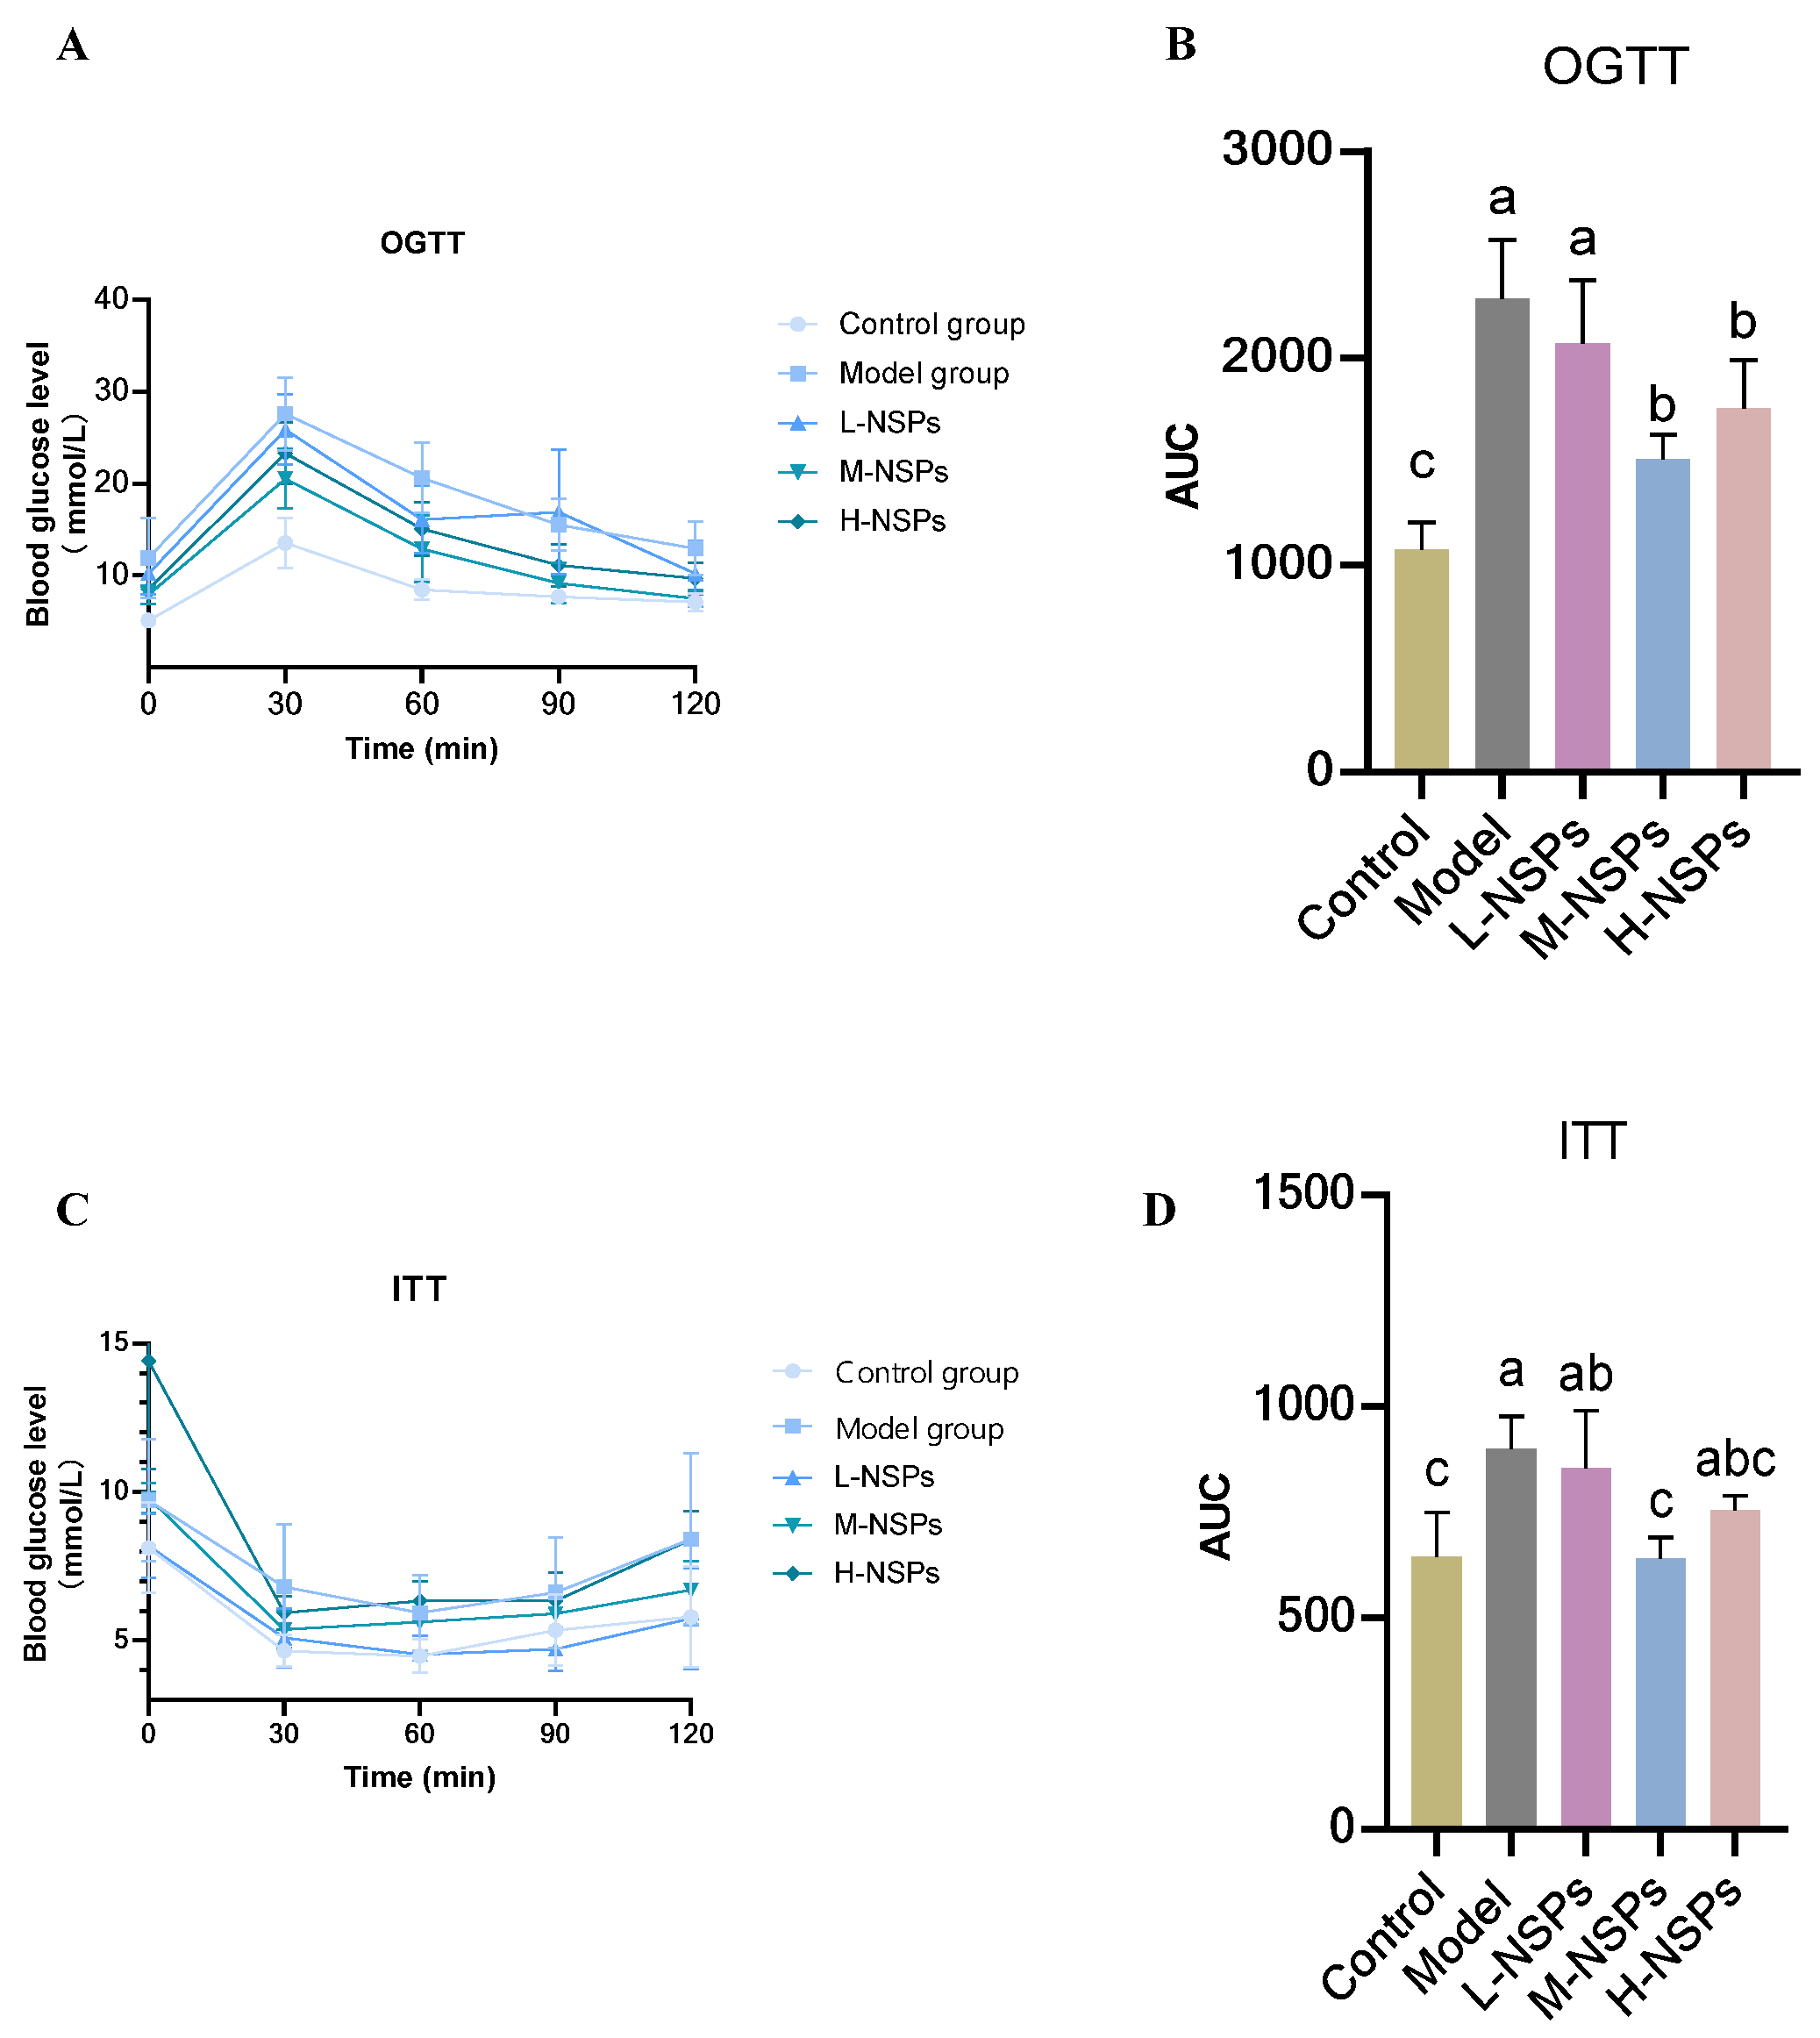

3.5. The Effect of NSPs on OGTT and ITT in the Diabetic Mice